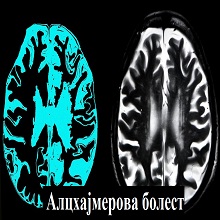

| Деменција се дефинише као стечени и перзистентни поремећај интелектуалних функција са дефицитом у најмање три од следећих интелектуалних функција: 1. памћење, 2. језик, 3. виднопросторне способности, 4.личност и понашање, 5.друге когнитивне способности (апстрактно мишљење, рачунање, планирање). Кључно је да когнитивне промене морају бити стечене и довољно изражене да ремете социјални и професионални живот болесника. |

Алцхајмерова болест (АБ) дефинисана је као клиничко-патолошки ентитет који најчешће има амнестичку презентацију (почиње поремећајима памћења, а праћен је развојем прогресивне деменције у следећих неколико година). |

Тренутно, више од 55 милиона људи широм света има деменцију, од којих преко 60% живи у земљама са ниским и средњим приходима. Сваке године има скоро 10 милиона нових случајева. |